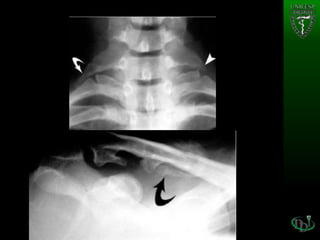

• #19 - Cervical plain radiograph of a 27-year-old woman shows both a cervical rib (arrow) and an elongated C7 transverse process (arrowhead). - Excessive callus of the clavicle in a 36-year-old patient with neurologic TOS. Anteroposterior plain radiograph of the clavicle